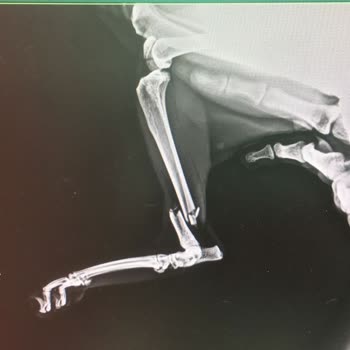

02.09.2025 tarihinde kedimin aşısı için İstanbul Kartal Cevizli ’deki Papyon Veteriner Kliniği’ne başvurdum. Kliniğe girer girmez kedim muayene edildi ve ciddi bir problemi olduğu söylenerek hemen röntgen ve kan tahlili yapıldı. Sonrasında toplam 6.700 TL fatura çıkarıldı. Bu durumdan şüphelendiğim ...